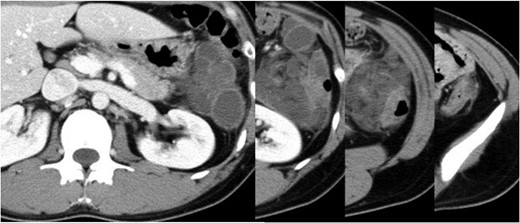

Abdominal enhanced CT showing multiple cysts with inflammation in the descending mesocolon.

Mesenteric and mesocolonic lymphangiomas are usually asymptomatic; any related symptoms are variable and non-specific, depending on the lesion size and location, although a palpable abdominal mass and abdominal distension are most common [4, 6]. Intra-abdominal cystic lymphangiomas infrequently present with acute abdomen, including bowel obstruction, volvulus, bleeding and infection [7]. In total, 90% of lymphangiomas become symptomatic before a mean age of 2 years [1]; therefore, it is uncommon for cystic lymphangiomas of the mesocolon to cause severe, life-threatening abdominal symptoms in adults [8]. The chief symptom in our case was severe abdominal pain with signs of peritoneal irritation due to inflamed cystic lymphangiomas. Ultrasonography (US) is an appropriate modality for evaluating acute abdomen and it is valuable for diagnosing cystic lesions [2, 7]. However, CT and magnetic resonance imaging (MRI) are superior to US in terms of providing detailed information about lesion size, location and extent of spread [8]. MRI provides more precise differentiation from other cystic-like masses. However, in emergency cases, CT plays a key diagnostic role, given its wide availability and quantity of information provided [7]. Lymphangiomas of the mesocolon must be distinguished from other fluid-filled lesions, such as pseudocysts, dermoid cysts, enteric duplication cysts, lymphocoele, mesothelioma, lipoma and various types of sarcoma [9]. In our case, CT showed cystic lesions with peripherally enhancing rims and surrounding inflammation that corresponded with the painful region and were suspected to correlate with peritonitis; the differential diagnosis included lymphangiomas and other cyst-forming diseases.